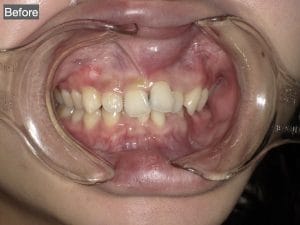

Case003

「昔から歯並びが気になっているので治したいが、もうすぐ海外に行くので時間がない」

「可能な限り安く、できるだけ自分の歯は削らないで綺麗に見えるようにして欲しい」

という患者様の症例です。

【治療内容】

上4本下4本 オールセラミッククラウン

【治療期間】

1ヶ月

【治療費】

840,000円

担当:理事長 佐藤悠野

Before写真にある下顎の最も前に出ている前歯を矯正なしで治療するために、神経をとる必要があった